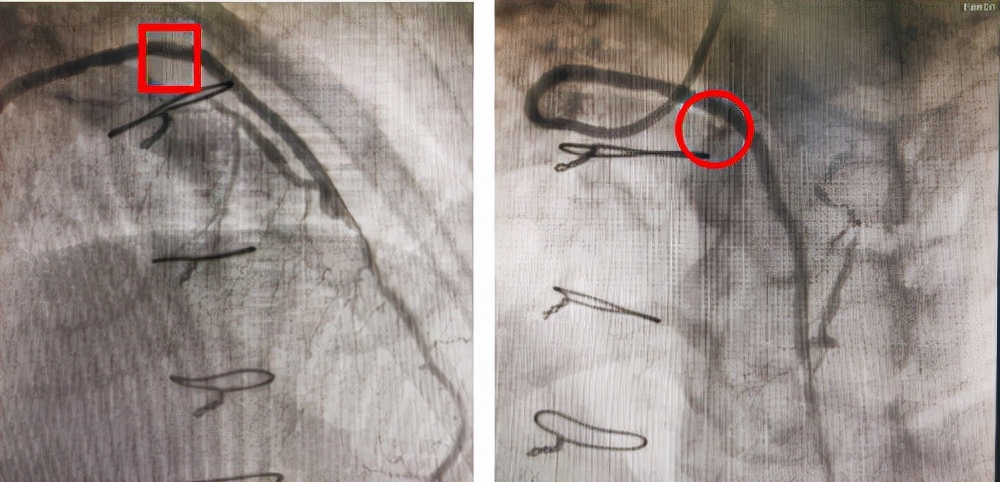

右冠静脉桥血管药物球囊治疗前后影像对比